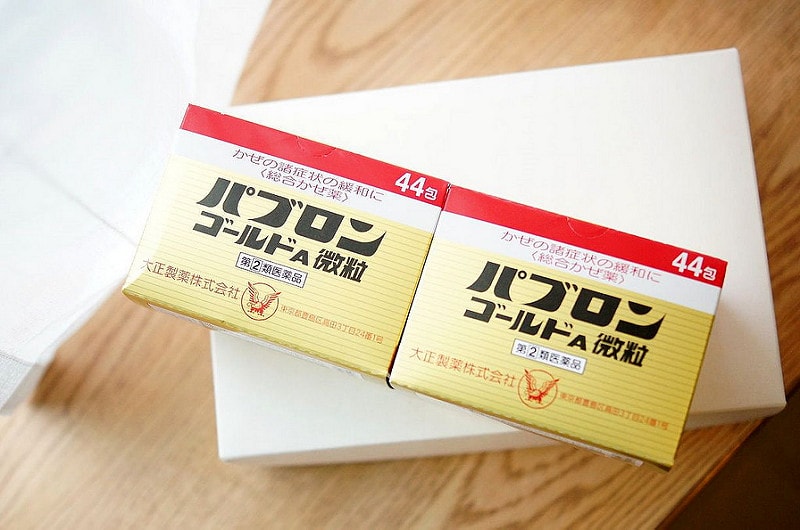

這也是感冒藥

是大正製藥家出的パブロン ゴールド a 微粒